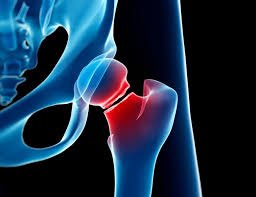

أعود مجدداً لأتحدث في تسلسل هذه التغريدة عن موضوع هشاشة العظام كما قمتم بإختياره في تصويتكم السابق،يطلق هذا اللفظ على حالة العظم عندما تكون هشة وضعيفة حيث أن أي سقوط أو حركة قوية يمكن أن تكسر العظم حيث أن غالب الكسور يمكن أن تكون في العمود الفقري أو الورك أو عند مفصل الرسغ(اليد).

أكثر حالات كسور الهشاشة تكون في العمود الفقري يليها عظمة الورك وأخيرا في مفصل الرسغ.

تعتبر كسور العمود الفقري أو الورك الناتجة عن هشاشة العظام من أكبر وأشد المضاعفات التي قد تؤدي إلى إعاقات أو خطر الوفاة لا قدر الله خصوصا في العام الأول من الإصابة كما أثبتت بعض الأبحاث.

بعد معرفة مشاكل ومضاعفات العظام أحب أن أبشركم أن هناك فحص لقياس كثافة العظام-dexa scan والذي بدوره يمكن أن يكشف حالة وكثافة العظام قبل حدوث أي مشكلة وكذلك متابعة فترة العلاج وهذا الفحص يعتبر الأدق والأقل عرضة للإشعاع ويتم عمله لفقرات الظهر L2-L4(الفقرةالقطنية ٢-٤) وكذلك الوركين.